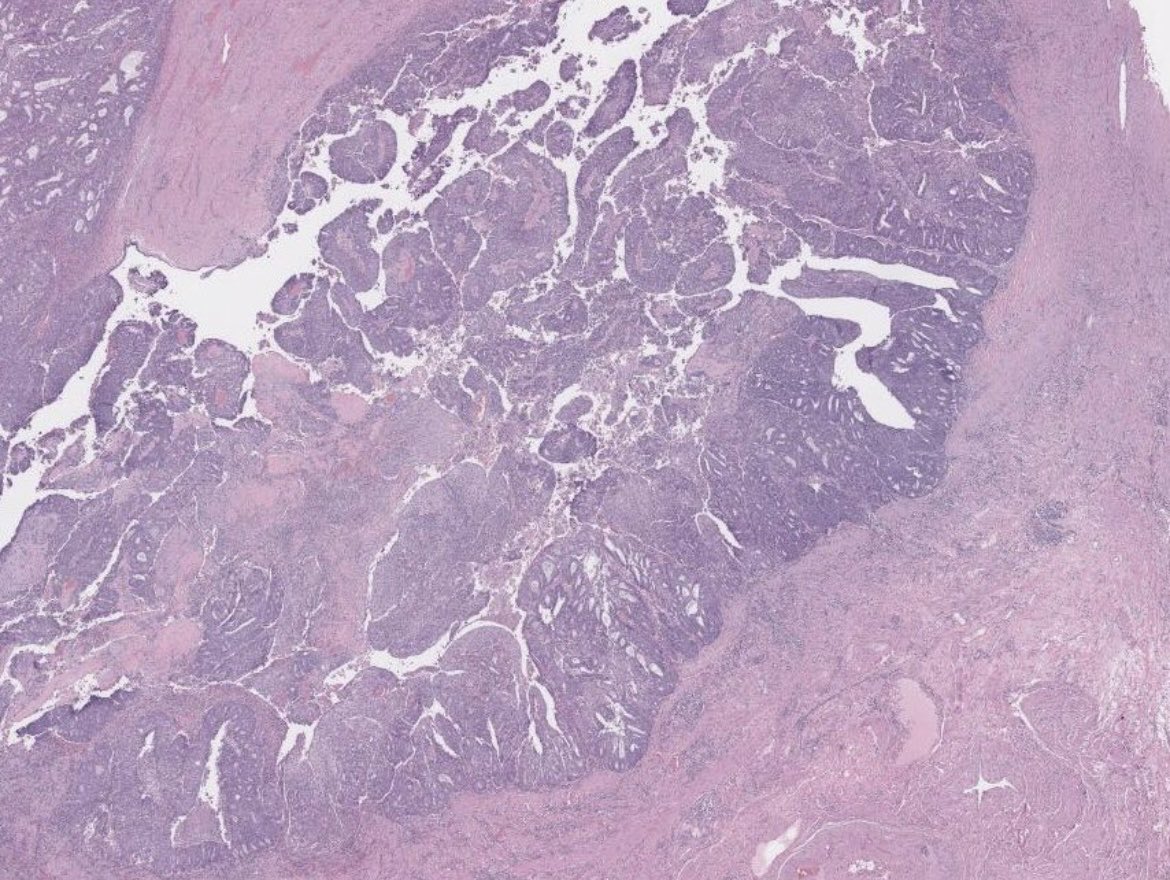

#Gynpath #Surgpath #pathresidents #Pathtwitter Some images of an endometrioid-type adenocarcinoma of the ovary in a 60-year-old woman. Mismatch repair proteins MLH1 and PMS2 show loss of staining (note negatively-staining tumor cell nuclei, with positively-stained stromal

Some images of an endometrioid-type adenocarcinoma of the ovary in a 60-year-old woman.

Mismatch repair proteins MLH1 and PMS2 show loss of staining (note negatively-staining tumor cell nuclei, with positively-stained stromal